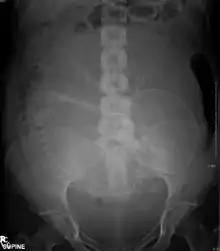

Abdominal radiograph of a pregnant woman

Diagnostic X-rays (primarily from CT scans due to the large dose used) increase the risk of developmental problems and cancer in those exposed.[105][106][107] X-rays are a form of ionizing radiation, and are classified as a carcinogen by both the World Health Organization's International Agency for Research on Cancer and the U.S. government.[99][108] It is estimated that 0.4% of current cancers in the United States are due to computed tomography (CT scans) performed in the past and that this may increase to as high as 1.5–2% with 2007 rates of CT usage.[109]

The risk of radiation is greater to a fetus, so in pregnant patients, the benefits of the investigation (X-ray) should be balanced with the potential hazards to the fetus.[119][120] If there is 1 scan in 9 months, it can be harmful to the fetus.[121] Therefore, women who are pregnant get ultrasounds as their diagnostic imaging because this does not use radiation.[121] If there is too much radiation exposure there could be harmful effects on the fetus or the reproductive organs of the mother.[121] In the US, there are an estimated 62 million CT scans performed annually, including more than 4 million on children.[109] Avoiding unnecessary X-rays (especially CT scans) reduces radiation dose and any associated cancer risk.[122]